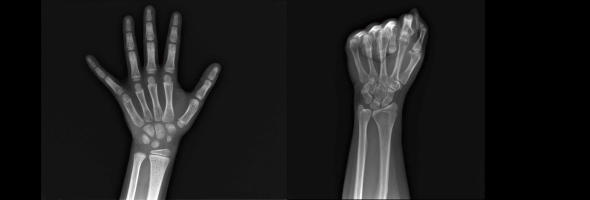

在骨骼健康管理中,“骨龄”与“骨密度”常被并列提及,但二者本质截然不同:前者是生物年龄的“时间刻度”,后者是骨骼质量的“密度标尺”。本文将从医学原理、检测技术、临床意义三个维度,揭开这对“双生密码”的神秘面纱。

骨龄与骨密度有什么区别?解析两者的定义、检测与应用

中华05标准骨龄检测:精准评估儿童发育,解码成长密码

在儿童健康管理领域,骨龄检测如同“成长密码”,精准解码孩子的生物学年龄与发育潜力。它不仅反映生物学年龄,更预示着身高潜力乃至代谢健康。本期我们就来探讨一下中华05骨龄评测标准,看看它为何在儿童生长发育领域备受关注。